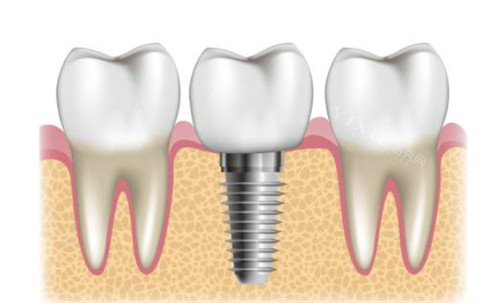

种植牙系列

单颗种植牙:3800元起(国产种植体)

进口种植体:6000~20000元/颗(韩国/欧美品牌可选)

半口种植(即刻负重技术):60000~120000元

全口种植(基础方案):50000~150000元(含骨增量手术需求)